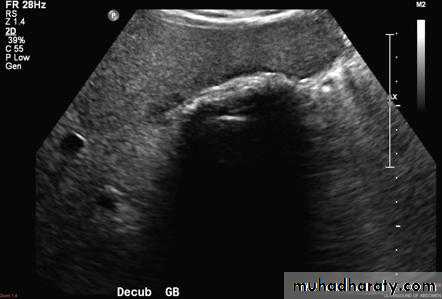

Cholecystitis

• US features of early or uncomplicated acute cholecystitis:

• Gall stones (which may be impacted in the GB neck or cystic duct)

• Gall bladder wall thickening

• Gall bladder distension

• Positive sonographic Murphy's sign (focal tenderness over the GB when compressed by the US transducer)

• US features of advanced or complicated acute cholecystitis:

• Pericholecystic fluid collection

• Striated appearance of the thickened GB wall

• Intraluminal membranes caused by sloughed GB mucosa

• Gas in GB wall or lumen resulting in emphysematous cholecystitis

• US features of chronic cholecystitis are thick wall and GB contraction.